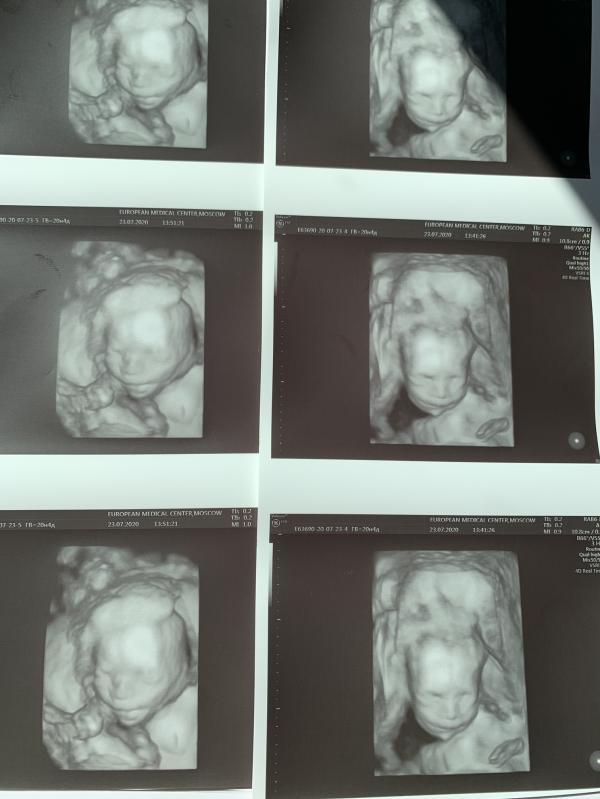

Наши 20 неделек и очередной поход на узи.

Мои пельмешки нажирают щечки, лежат оба в головном, у мамы в лобке... 😅 из за чего моя походка - аля только слезла из позы наездницы😅😅

Дети еще такие крохи, а уже такие характерные! Не любят они , когда их беспокоят. На узи закрывают лицо ручками, отворачиваются. Наш папа никак не Может поймать пинки, кладет руку, и они тут же затихают 🤷🏻♀️